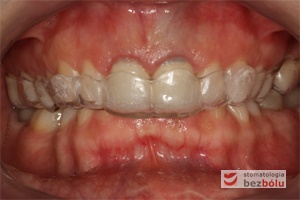

Pozycjonery to system przezroczystych nakładek precyzyjnie dopasowanych do łuków zębowych pacjenta, które przesuwają zęby w odpowiednio zaplanowane i wyznaczone przez lekarza ortodontę miejsca. Stanowią one alternatywne rozwiązanie dla aparatów stałych i ruchomych, jakkolwiek zakres wskazań do ich stosowania jest mocno ograniczony w porównaniu z aparatami stałymi. Są wykonywane indywidualnie dla każdego pacjenta, przez wykwalifikowanego technika dentystycznego.

- Estetyczne – są przezroczyste co pozwala bez skrępowania mówić i szeroko się uśmiechać.